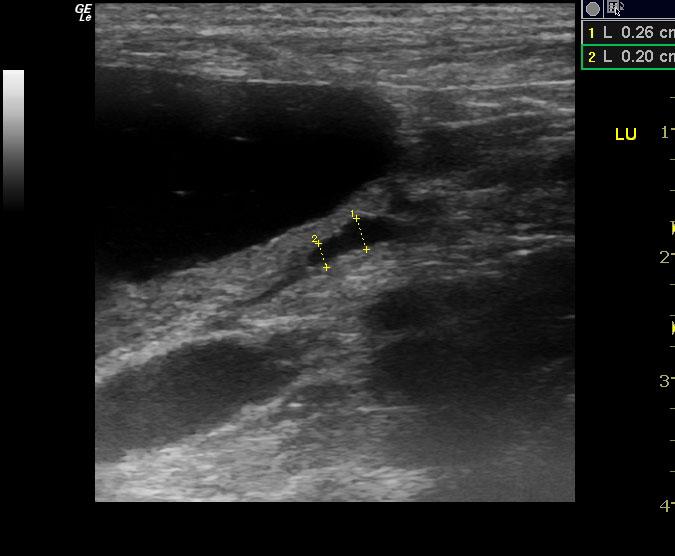

A 10-year-old SF American Eskimo with a history of bladder transitional cell carcinoma that had been stented, chronic renal insufficiency, hydronephrosis, and hydroureter, was presented for evaluation. CBC showed anemia (14%).